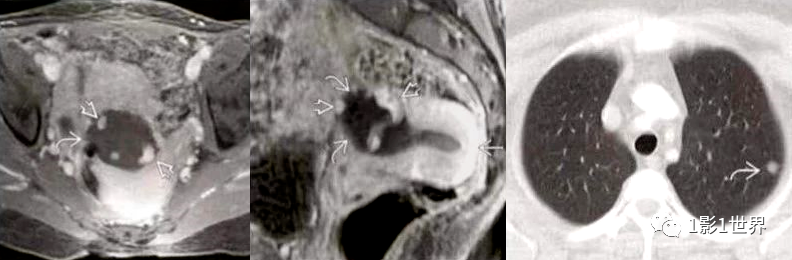

侵袭性葡萄胎,极少数绒毛变性可侵入到肌层,甚至发生远处转移。从组织学上看,属于水泡状胎块,不属于肿瘤。

影像诊断

MRI检查

增强扫描:表现为在扩张的子宫内膜腔内含有多个小囊腔样强化的异质组织,动脉期轻度不均匀强化,静脉期及延迟期渐进性网格状强化;宫旁见多发迂曲流空信号影,增强后可呈血管样强化